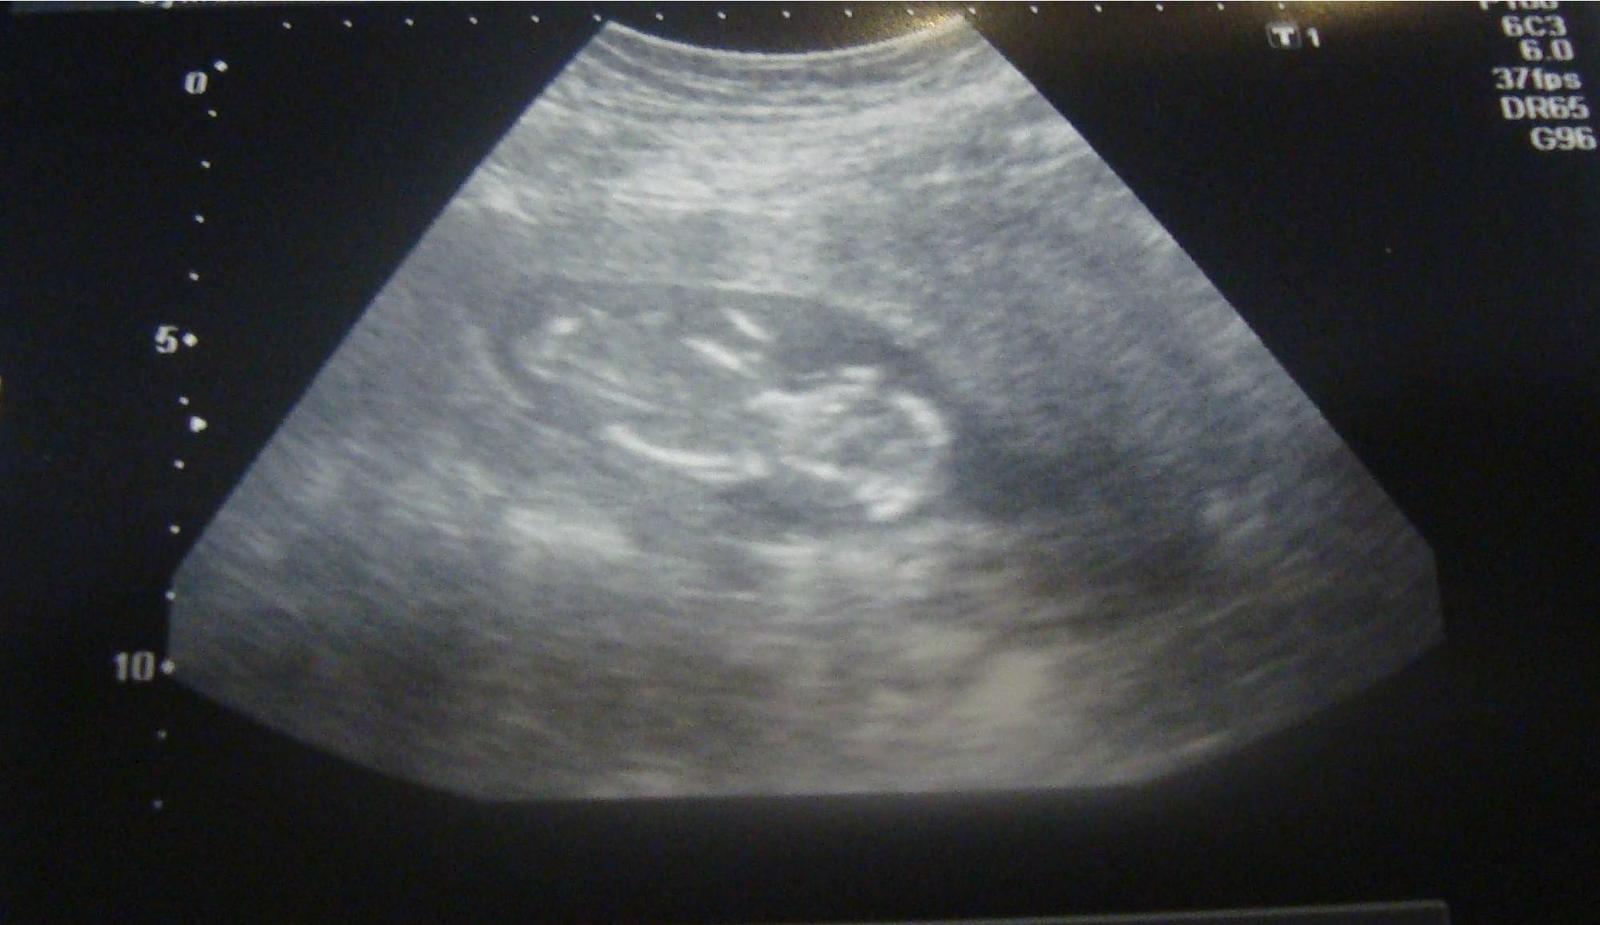

ahojte, tak kontrola dopadla super, az na zvyseny krvny tlak, mam brat magne b6 2x denne a merat si doma tlak kazdy den. ak presiahne 140/90 musim ist ihned k dr. a naspat na pn potom ☹. inak na krv kvoli triple testom idem 18.2. a poradnu mam 26.2.. takze zajtra sa ide do prace a uz mozeme aj cvicit aj sexikovat ale s mierou 😀 ! prikladam foto, kde uz pekne vidno chrbticu a meral mi uz len hlavicku plodu - 2cm 🙂